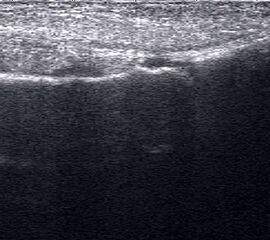

Referenzstruktur: Direkt unter der Haut und der dünnen Subkutis liegt echogen und straff parallel die Achillessehne mit ihrem echogenen Peritendineum.

Befunde: Klassischerweise findet sich eine normal echogene spindelförmige Verdickung einige Zentimeter über der Insertion (Abb. 60). In der Frühphase zeigen Tendinopathien eine echoarme Verdickung. Im Verlauf finden sich zunehmend echogenere Bezirke und Inhomogenitäten, teilweise mit Einziehungen und rau erscheinendem Peritendineum. Ist die Sehne teilweise nicht mehr abgrenzbar, kann bereits ein Übergang in eine teilweise Kontinuitätsauflösung vorliegen. Ein peritendinöser Randsaum ist vor allem in frühen Phasen zu beobachten. Flüssigkeitsareale, die von der echogenen Sehne abgrenzbar sind, sprechen jedoch auch an der Achillessehne für eine Rissbildung. Auch Kalkeinschlüsse oder peritendinöse Verkalkung mit Schallschatten sowie intratendinöse Zysten werden beobachtet.